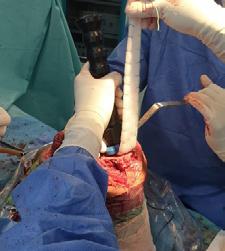

În a doua etapă, după parcurgerea curei antibiotice, se practică revizia cu implantele finale, folosind proteza de revizie de tip balama, cu stem femural și tibial lung, cu protecția oferită de perlele de Stimulan impregnate cu Vancomicină și Linezolid.

Particularitatea cazului o oferă tipul de tehnică chirurgicală folosită în refacerea ligamentului rotulian prin utilizarea unei grefe sintetice, de tipul Marlex mesh. (3) Din experiența noastră folosind multiple tipuri de grefe pentru reconstrucția ligamentului rotulian, rezultatele în timp s-au dovedit ineficiente (evaluarea la 1-3 ani postoperator indică resorbția cu dispariția ligamentului rotulian în întregime în mediu aseptic după folosirea grefei din Banca Națională de Țesut, fiind utilizată atât grefă cu pastilă osoasă calcaeană și tendon Achillean, cât și aparat extensor

întreg – dar osteointegrarea osoasă la nivelul TTA fiind completă), motiv pentru care am decis utilizarea unui substitut alloplastic- meșă (plasă) de polipropilenă 30x30cm care a fost preparată astfel: bucata de material a fost pliat în 8 straturi, având o l=3cm și o L=30 cm, fiind suturată cu fir neresorbabil pe lateralele sale, urmând a fi cimentată in canalul tibial odată cu componenta protetică tibială. După stabilirea indicelui Insall-Salvati corect, s-a folosit o langetă musculară din dreptul femural după tehnica Ducroquet care a acoperit noul ligament sintetic, oferind protecție si bază nutritivă și a fost stabilizat cu ajutorul a 2 ancore cu fire nerserobabile (Fig 4+5+6). Postoperator pacientul este imobilizat în aparat gipsat femuro-gambier pentru 6 săptămâni, mărind treptat gradul de flexie.